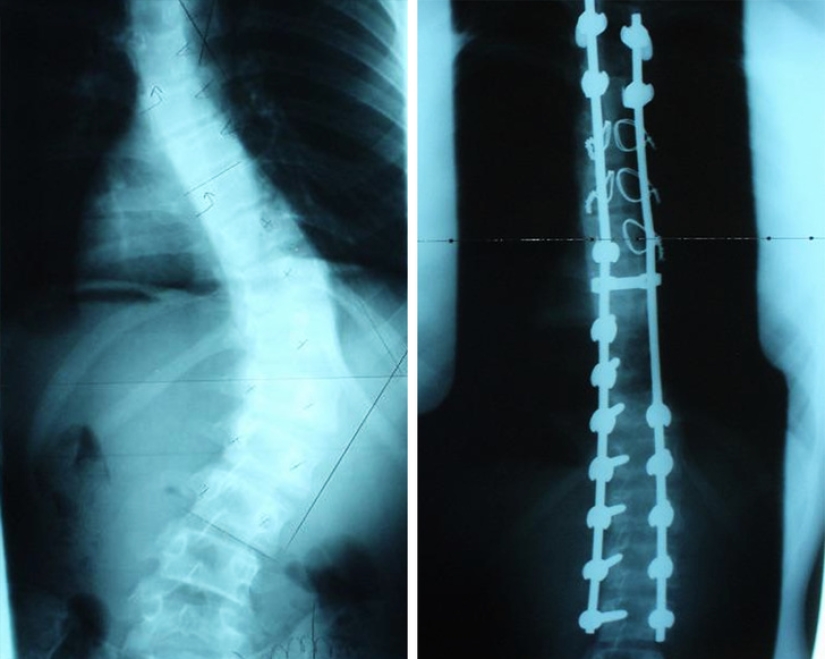

X-ray before and after surgery to correct scoliosis.